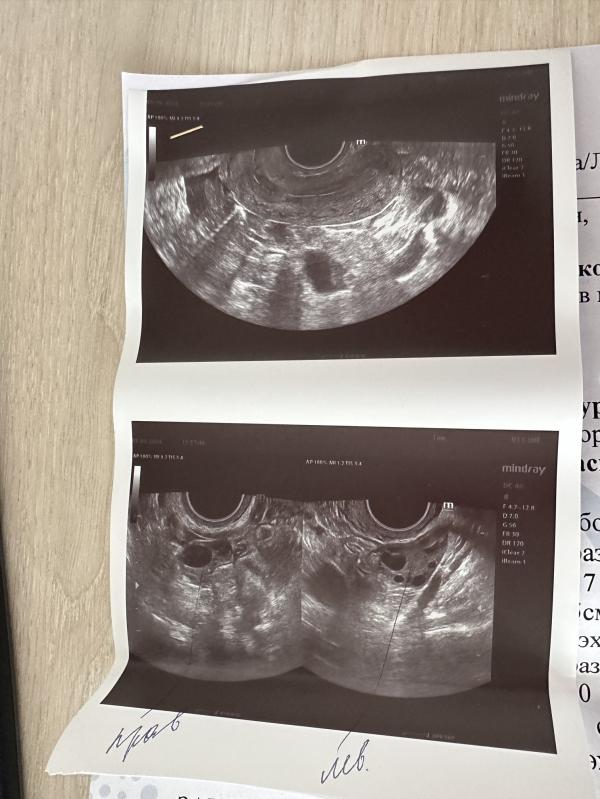

Фолликул 14,5 мм, лопается в среднем от 20 мм и растет по 2 мм в сутки

Значит где то в пятницу может лопнуть

У меня фолликул был 14 и лопнул через 6-7 дней. Но у всех по разному. В среднем растет 1,5-2 в день.